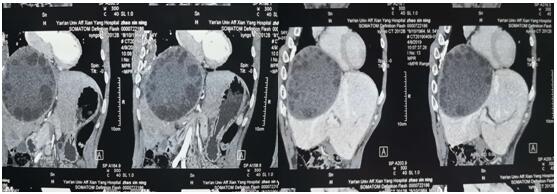

術(shù)前CT和三維重建

患者入科,姚春和主任與科室醫(yī)師通過細(xì)致的診查,即確診該患者系“肝臟巨大肝包蟲”。此病例較為罕見,手術(shù)難度大。經(jīng)嚴(yán)密術(shù)前討論,姚主任操刀,于4月16日在全麻下行巨大肝包蟲外囊摘除術(shù)。術(shù)中嚴(yán)格無菌保護周圍組織,細(xì)致剝離血管,手術(shù)歷經(jīng)4小時,成功摘除大小約20*30cm包蟲外囊。此例手術(shù)的完成標(biāo)志著我院肝膽外科在肝臟手術(shù)的又一巨大突破。